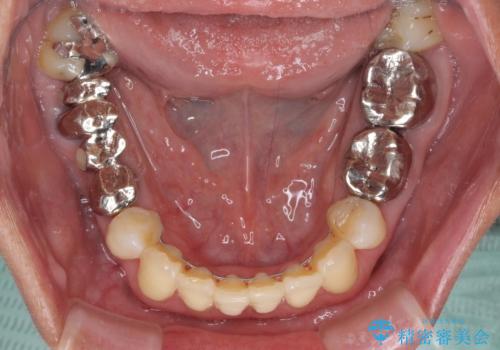

- 上の前歯の変色と、下の前歯のデコボコを気にして来院された患者様です。

前歯はオールセラミッククラウンに補綴することとしました。

補綴治療に先立ち、下顎前歯の部分矯正を行い、前歯の咬み合わせの安定性向上を図りました。